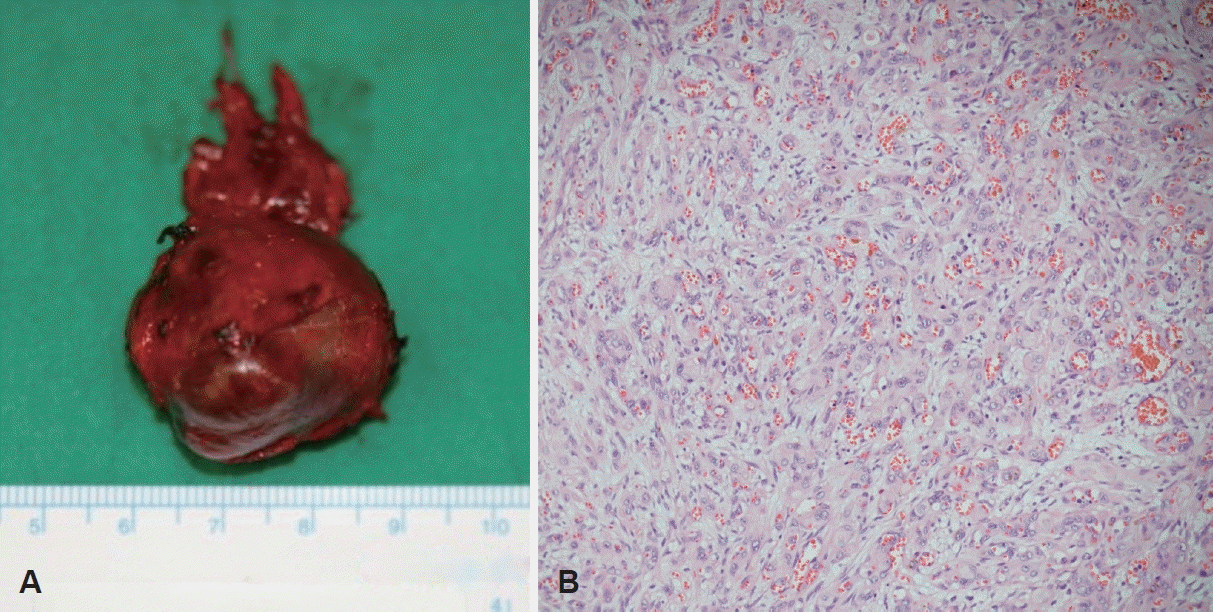

After the mediastinal mass was ultimately judged to be malignant and considered a tumor for which surgical resection should take priority, we planned complete excision under general anesthesia. Anticipating a risk of injury to major vessels and the need for a wider operative field, we proceeded via a cervical approach with a thoracic surgeon available. Owing to the prior incisional biopsy and the malignant nature of the lesion, there were substantial adhesions around the mass. The mass was firm, well consolidated, involving the left upper mediastinum and the paraesophageal space. It was located inferior to the common carotid artery, medial to the jugular vein and vagus nerve, and lateral to the tracheoesophageal groove and recurrent laryngeal nerve. It was connected to branches of the subclavian artery and vein, including the thyrocervical trunk, and was also connected to the thoracic duct. We achieved complete resection by carefully dissecting the surrounding tissues while establishing a safe dissection plane (Fig. 5A). Although the mass was adherent to the subclavian and internal jugular veins, there was no direct invasion, and complete separation was possible, so venous ligation was not performed. Histopathology of the completely resected mass also confirmed epithelioid hemangioendothelioma (Fig. 5B).

Completely-excised specimen demonstrates a 3.5 cm sized somewhat round bumpy dark reddish to light brownish colored solid mass with multiple visible hemorrhagic spots on the surface grossly (A), and the tumor is comprised of cords and nests of atypical endothelial cells with numerous small vascular lumina containing erythrocytes microscopically (B, hematoxylin-eosin stain, ×200).